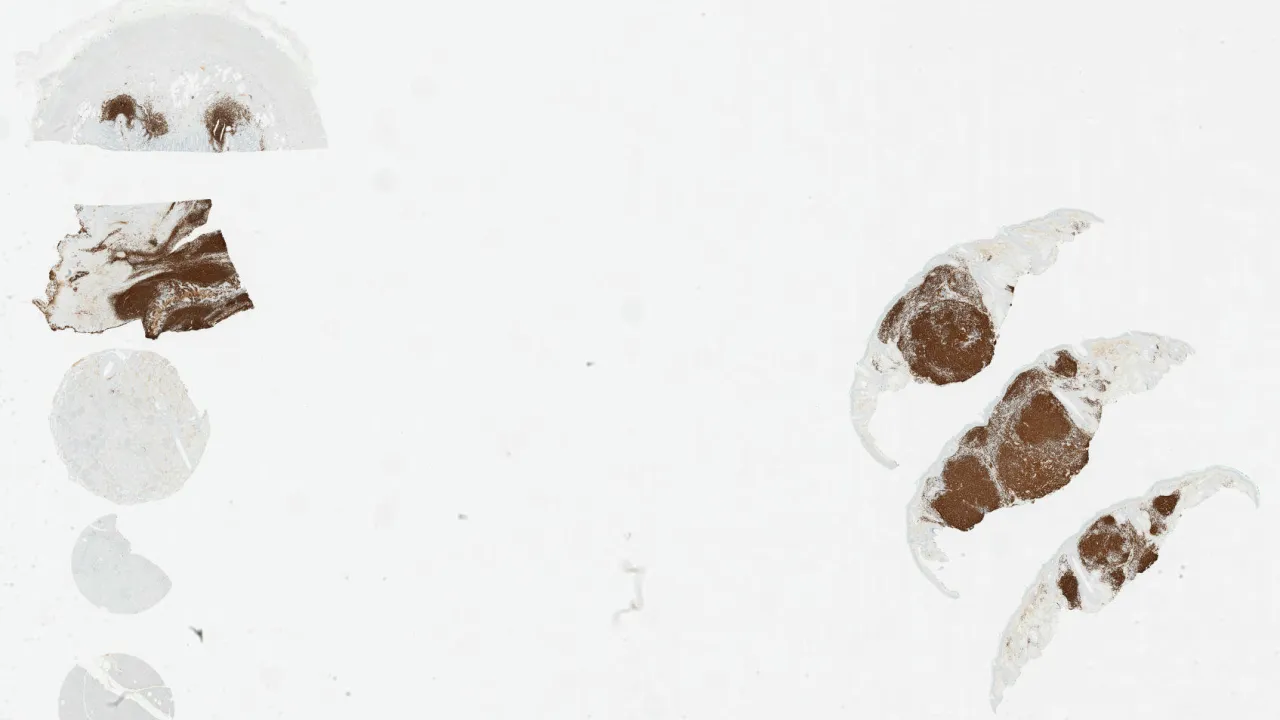

Lymph Nodes, Anaplastic large cell lymphoma, ALK negative, ALK1 stain

Lymph Nodes, Anaplastic large cell lymphoma, ALK negative, CD30 stain